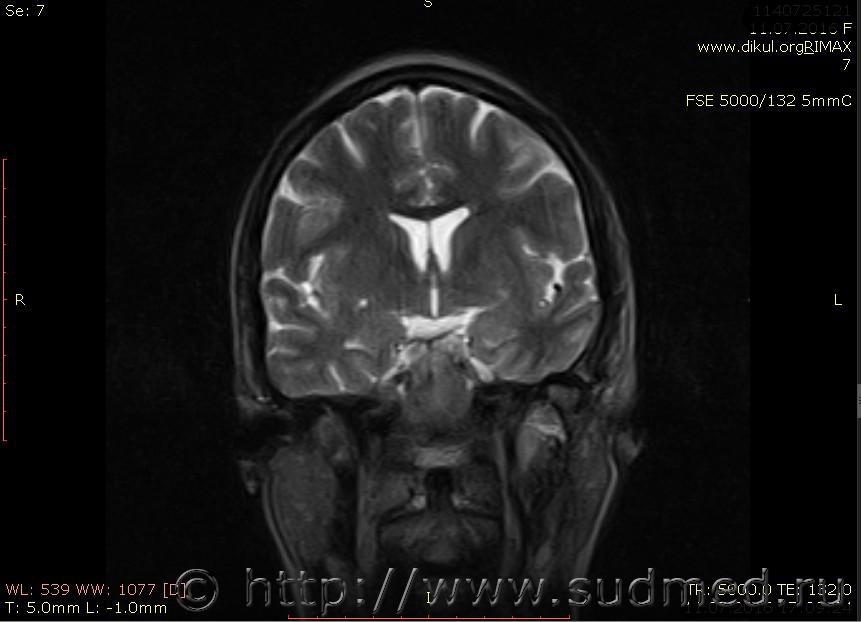

МРТ головного мозга показало: МР-данных за наличие очаговых изменений в веществе головного мозга на момент исследования не выявлено. МР-признаки нарушения соотношения в атланто-осевом суставе. Определяется ассиметрия положения зубовидного отростка С2 относительно боковых масс С1(справа 6,5; слева 4 мм.)

Сама по себе эта информация даёт основания подозревать вывих первого шейного позвонка, но однозначно не свидетельствует о наличии вывиха. Нужно смотреть на снимках наличие реакции со стороны мягких тканей, в т.ч. связочного аппарата, нужно анализировать особенности неврологической патологии, её динамику и проч.

Запрошен электронный вариант снимков из учреждения, где делалось МРТ. Т.к. с самого снимка делать копии не получается,очень мелкие кадры. Завтра попробую вставить в сообщение. (Но СМЭ снимок не смотрел, смотрел только мед.карту, в которой находилось описание МРТ).

Посмотрите пожалуйста снимки, надеюсь на них видны позвонки С1,С2?

Прошу прощения, попробую снова прикрепить файлы. Данные учреждения и пациента убраны.